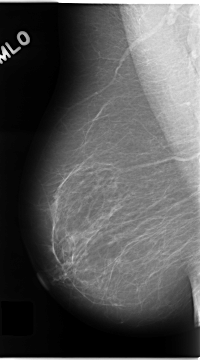

C_0138_1.RIGHT_MLO

RIGHT_MLO LINES 4680 PIXELS_PER_LINE 2600 BITS_PER_PIXEL 12 RESOLUTION 50 NON_OVERLAY